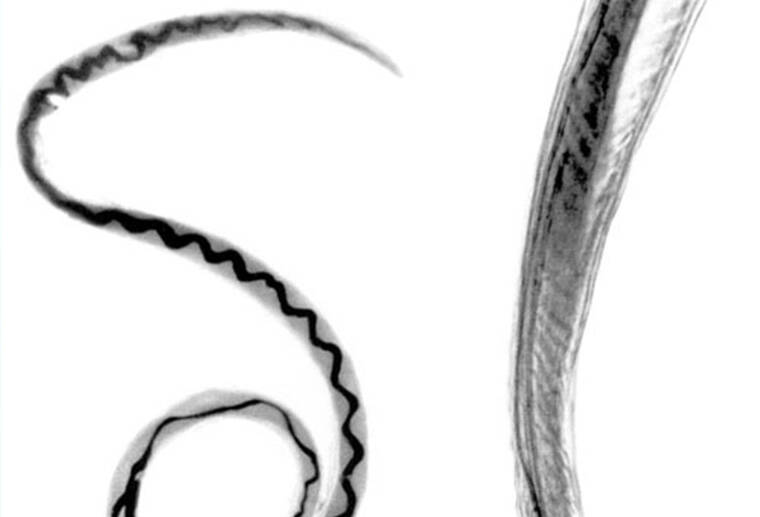

The rat lungworm parasite is seen through a microscope. The Hawaii Department of Health has confirmed a case of rat lungworm disease in an individual on the island of Kauai.

Rat lungworm disease, caused by a roundworm parasite called Angiostrongylus cantonensis, affects the brain and spinal cord and can result in long-term disability.

The parasite is only found in rodents, but infected rodents can pass larvae of the worm in their feces, which can then be ingested by snails, slugs, and some other animals such as freshwater shrimp or prawns, which then become intermediate hosts.